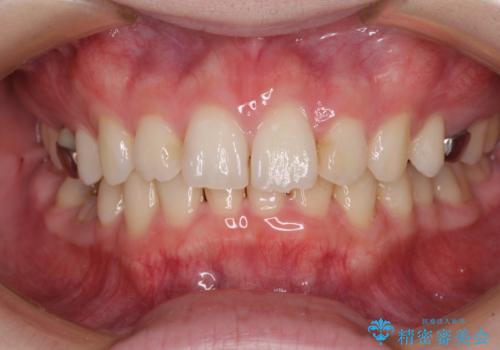

- 咬み合わせと前歯のデコボコを気にして来院された患者様です。

前から5番目の永久歯が3本欠損しており、乳歯が残存している状態でしたが、インビザラインでも十分に対応可能と判断し、インビザラインにて矯正治療を行うこととしました。

右下の残存している乳歯は萌出しきれておらず、全く咬み合っていない状態であり、インビザラインにて移動できない可能性があるため、ワイヤー矯正の併用も念頭に置いて治療を開始しました。